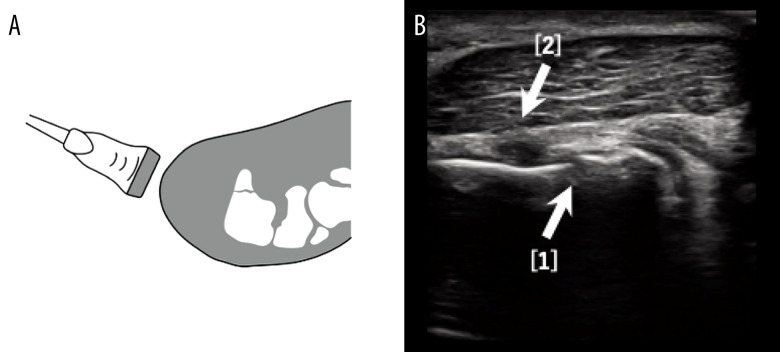

BACKGROUND Early diagnosing a stress fracture of the hook of the hamate is challenging with plain X-rays alone. However, it is necessary to determine the appropriate treatment method to allow athletes to return to sports as soon as possible. We present a case in which diagnosis of stress fracture of the hook of the hamate in a professional baseball player was confirmed on the day of injury by ultrasound imaging, and early intervention was performed. CASE REPORT The patient was a 22-year-old male professional baseball player. During hitting practice, he experienced pain in his right palm, then tenderness around the hook of the hamate was noted. Ultrasonography revealed disruption of the bony cortical continuity of the ulnar aspect of the hook of the hamate and a hematoma around this lesion. Stress fracture of the hook of the hamate was confirmed by computed tomography. Resection of the hook of the hamate was performed on the third day after injury. The patient returned to playing baseball 3 months after surgery. CONCLUSIONS In stress fracture of the hook of the hamate, the time required for diagnosis greatly affects the time to return to competition. To solve this clinical issue, ultrasonography was applied to the early diagnosis of stress fractures of the hook of the hamate. This study suggests that ultrasound can be a useful diagnostic tool for early diagnosis of stress fractures of the hook of the hamate.